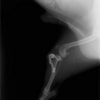

半年にわたる左後肢の跛行が認められるとのことで来院されました。触診にて左膝関節の疼痛、内側部の腫脹、膝蓋骨の内方脱臼を認めました。レントゲン検査にてfat pad signを伴う関節炎が認められたことから、前十字靭帯断裂と膝蓋骨内方脱臼( GradeⅢ)の併発と診断し、手術を行いました。術中の関節鏡検査にて前十字靭帯の完全断裂を確認、関節液検査にて感染を除外した後、TPLOと、滑車溝形成を始めとした膝蓋骨脱臼整復術を実施いたしました。

術前側面像

術前正面像

術後側面像

術後正面像

術前に25°であったTPAは、TPLO実施により7°に矯正されました。症例の歩行状態は良好です。